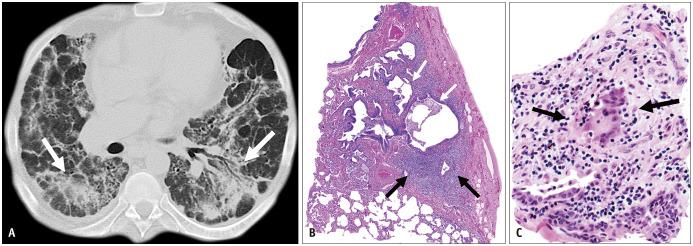

Non-infectious granulomatous lung disease represents a diverse group of disorders characterized by pulmonary opacities associated with granulomatous inflammation, a relatively nonspecific finding commonly encountered by pathologists. Some lesions may present a diagnostic challenge because of nonspecific imaging features; however, recognition of the various imaging manifestations of these disorders in conjunction with patients' clinical history, such as age, symptom onset and duration, immune status, and presence of asthma or cutaneous lesions, is imperative for narrowing the differential diagnosis and determining appropriate management of this rare group of disorders. In this pictorial review, we describe the pathologic findings of various non-infectious granulomatous lung diseases as well as the radiologic features and high-resolution computed tomography imaging features.